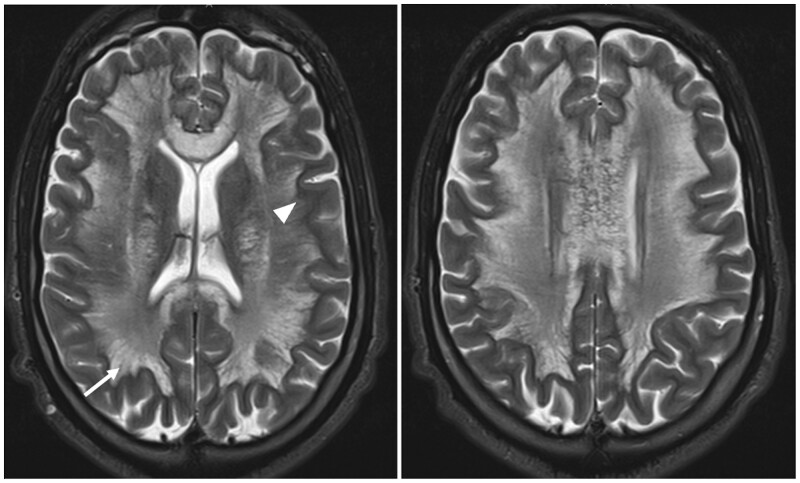

Heroin-induced leukoencephalopathy (HLE) is a rare toxic encephalopathy associated primarily with heroin inhalation, commonly referred to as "chasing the dragon." This study presents a clinical case of a 27-year-old polydrug user diagnosed with HLE during hospitalization for rapidly progressive flaccid tetraplegia and aphasia. The clinical manifestations encompassed cerebellar and bulbar dysfunction, coupled with motor impairment and altered consciousness. Based on the clinical data and MRI results, HLE was identified as the most likely cause. This article aims to provide insights into the clinical and radiological aspects of HLE, emphasizing the diagnostic significance of radiological findings. The gold standard examination for diagnosis is MRI, crucial due to the difficulties in obtaining histological confirmation for this rare condition.